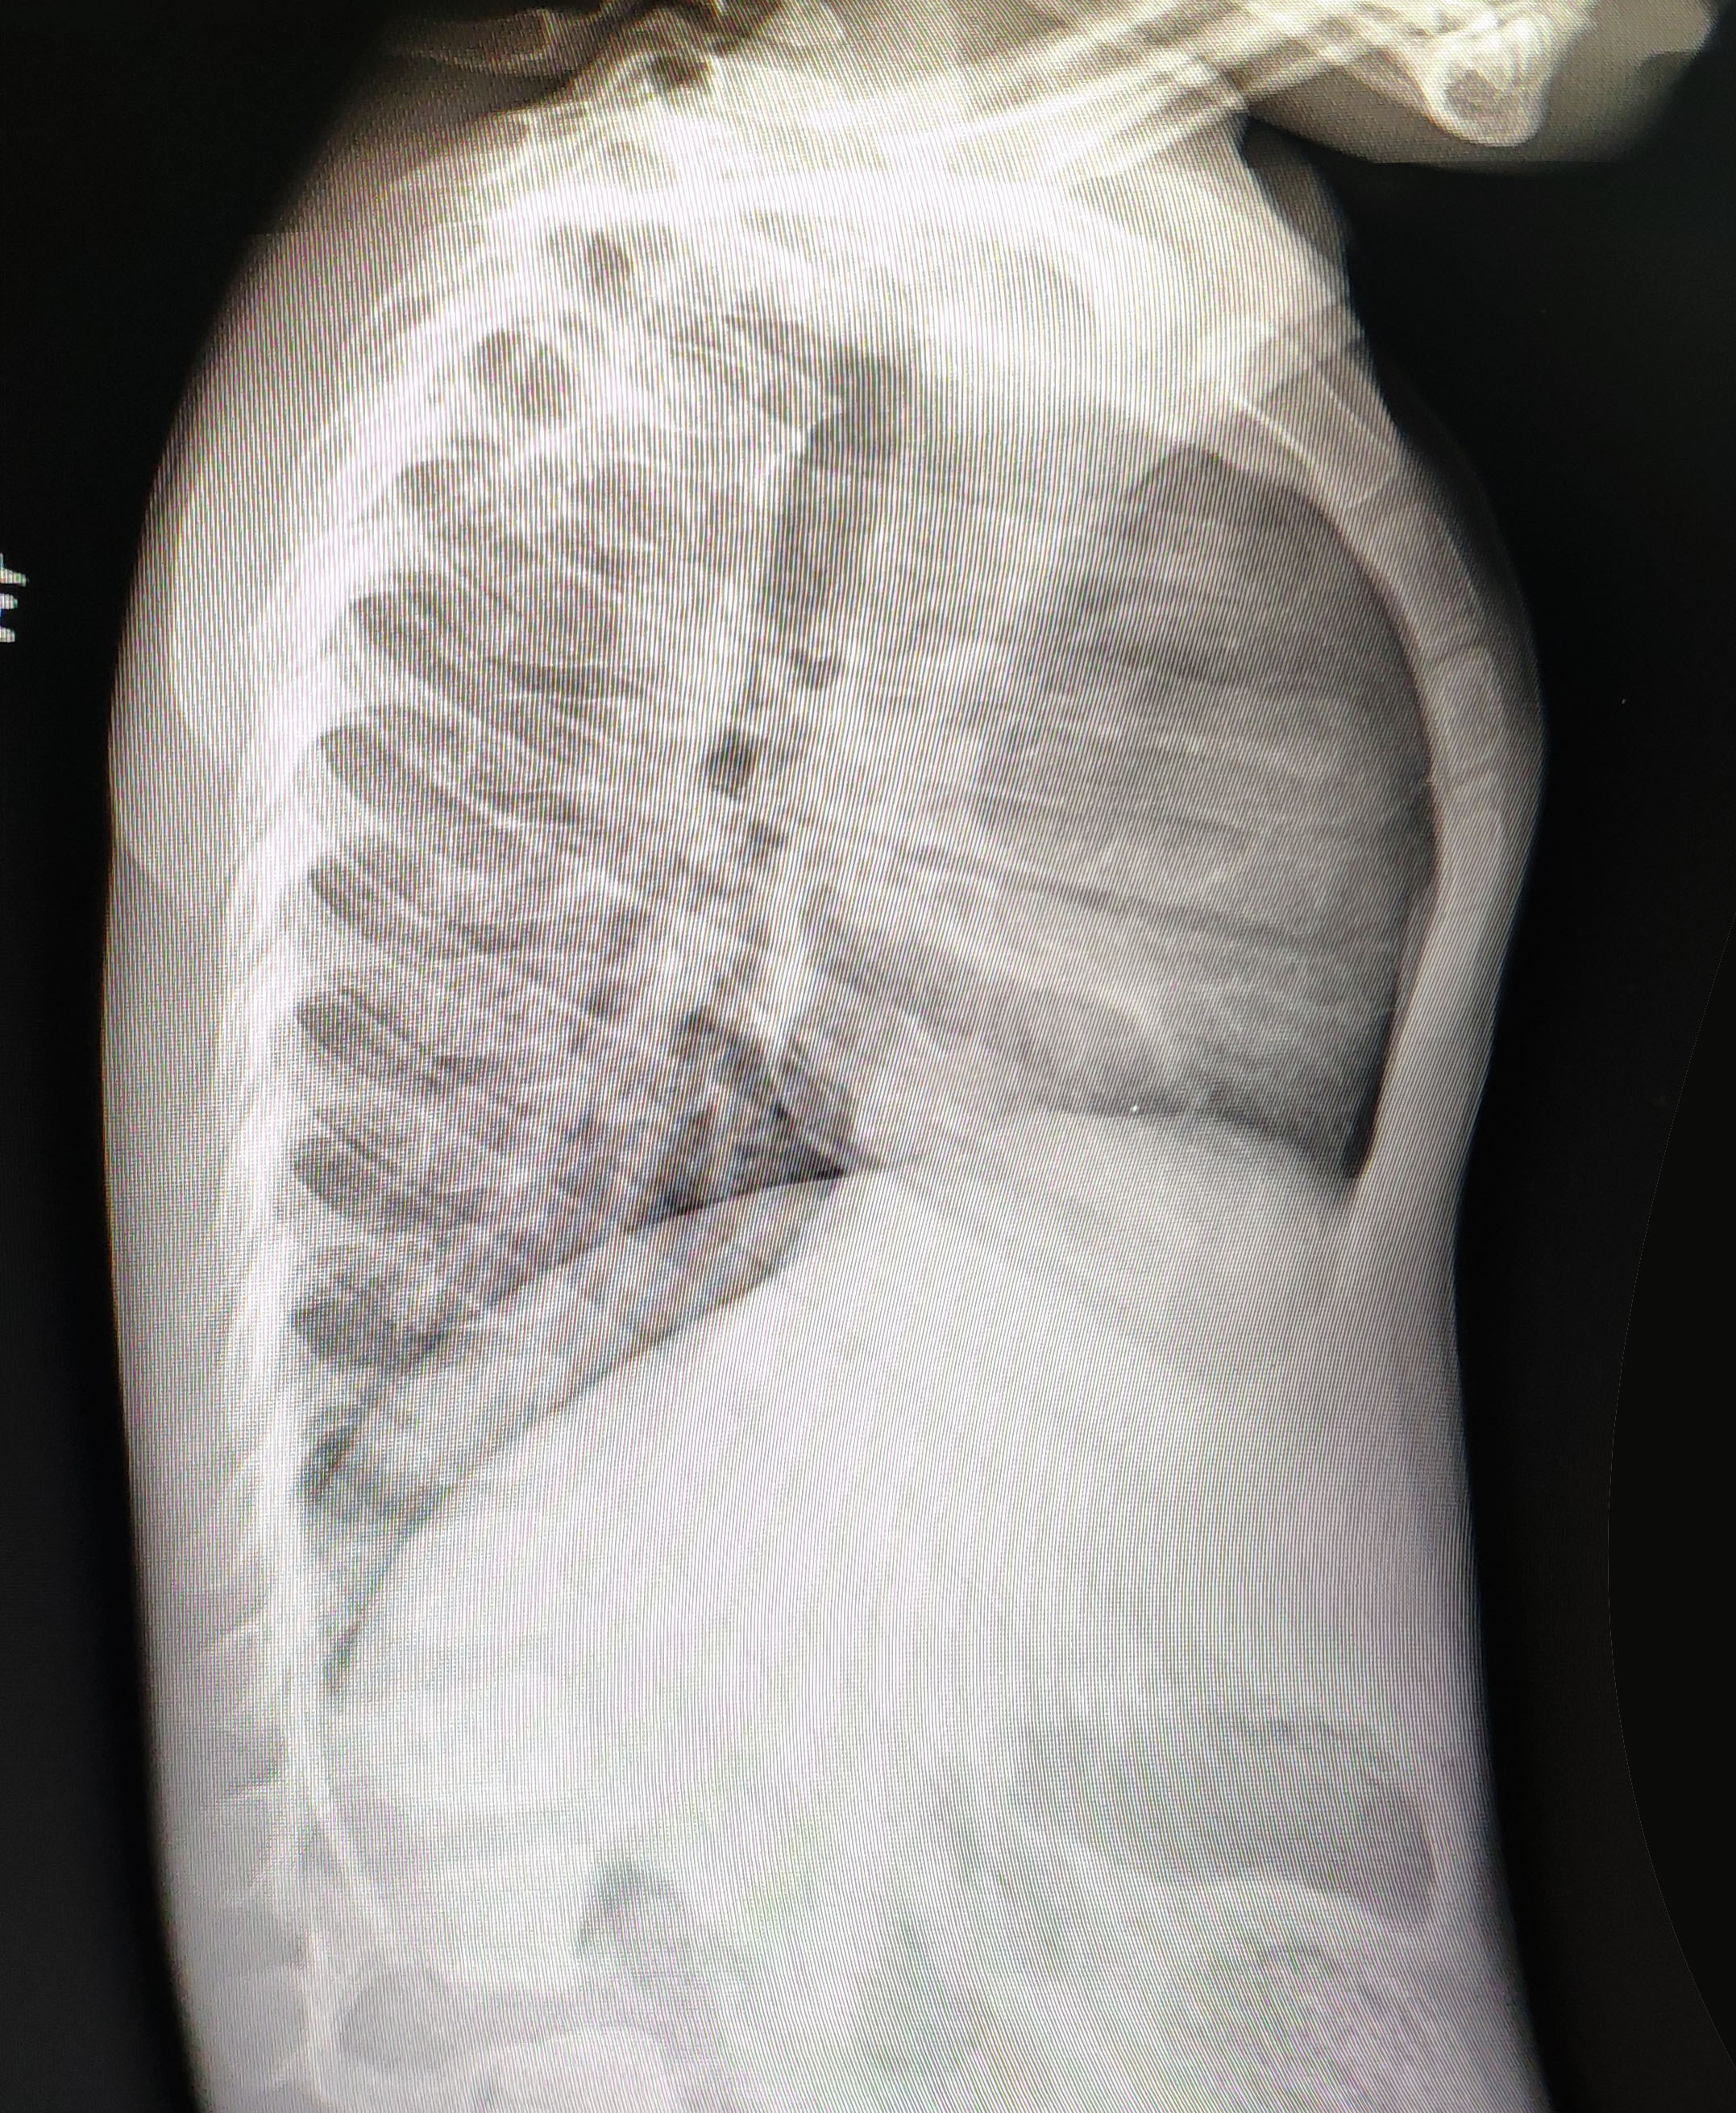

【提要】今天我们为一例4岁的患儿实施了鸡胸手术,术中采用我们设计的Wenlin手术完成治疗,获得了满意的效果。

今天的患儿非常特殊,年龄仅4岁,但鸡胸已经发现两年。过去曾认为因缺钙引起,大量补钙,补鱼肝油,但毫无效果。近来发现鸡胸加重,于是决定手术。

今天的手术在全麻下完成。全程无管,采用标准TUBELESS技术完成操作,手术方法为Wenlin手术。手术切口位于两侧胸壁,切口长1cm。以一条钢板塑形,手术历时30分钟完成。塑形效果满意,术后畸形完全消失。

今天的患儿年仅4岁,由于畸形已经定型,且逐渐加重,因此有明确手术指征。早期实施手术的优点非常明确,由于骨骼柔软,不但矫形容易,而且不需要太多的材料,这使得手术费用也明显降低。